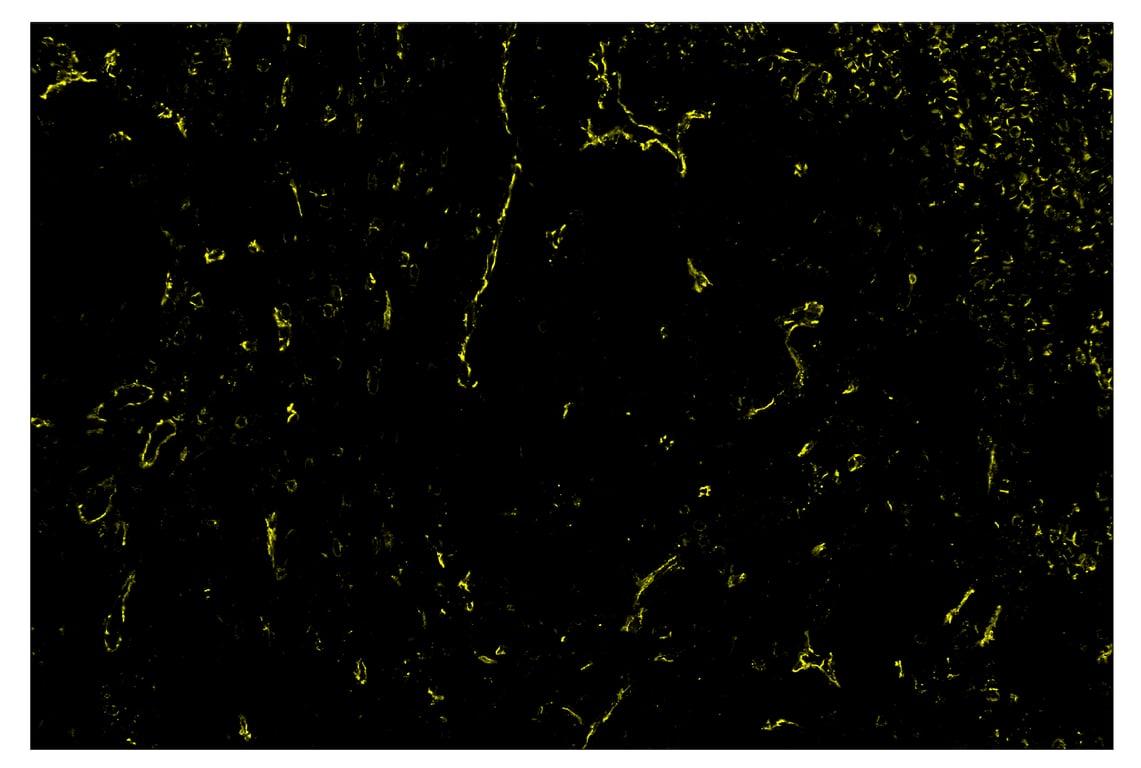

Immunohistochemistry Image 2: CD31 (PECAM-1) (89C2) & CO-0028-488 SignalStar<sup>™</sup> Oligo-Antibody Pair

SignalStar™ immunohistochemical analysis of paraffin-embedded human squamous cell lung carcinoma using CD31 (PECAM-1) (89C2) & CO-0028-594 SignalStar™ Oligo-Antibody Pair #33420 (yellow). All fluorophores have been assigned a pseudocolor, as indicated. Staining was performed on the BOND RX by Leica Biosystems.